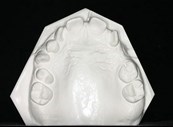

Dental Casts

right buccal frontal left buccal upper mandibular

Right Buccal View Frontal View Left Buccal View Maxillary View Mandibular View